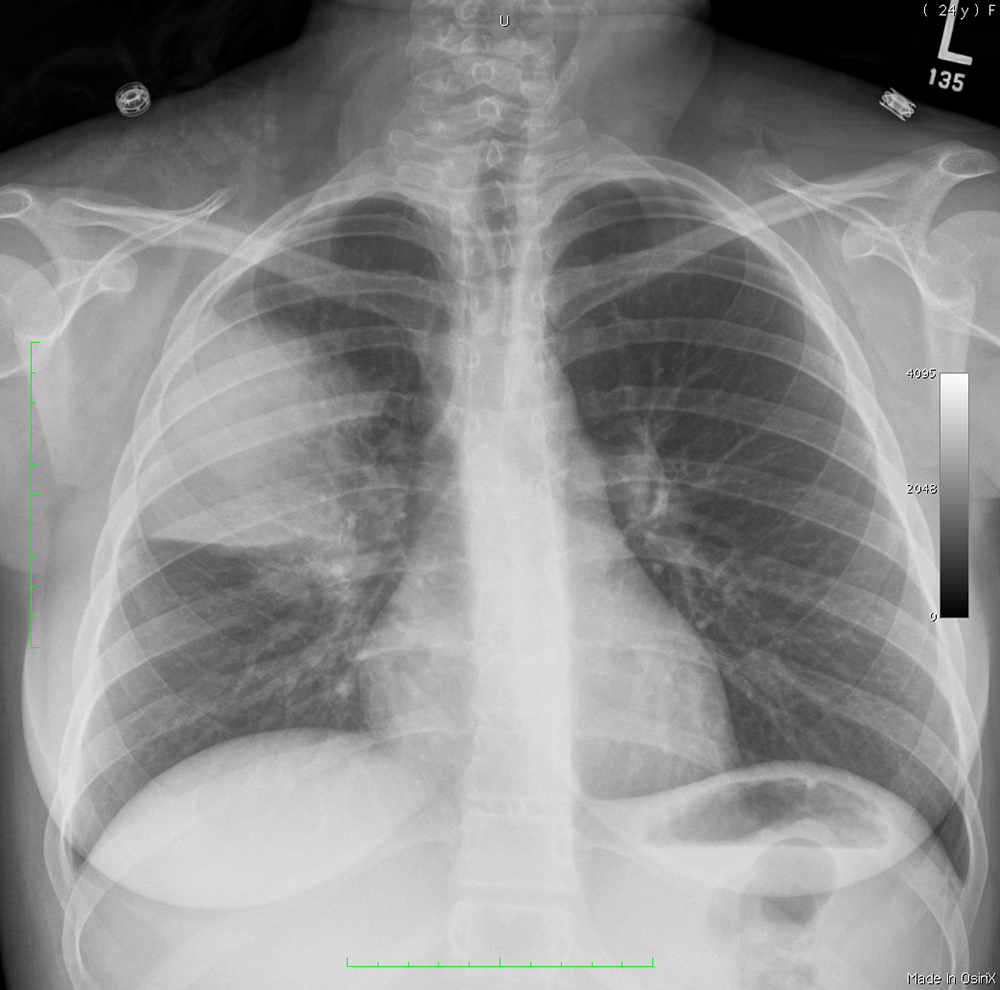

Topic 1

basic case-PNA

Further Explanation: